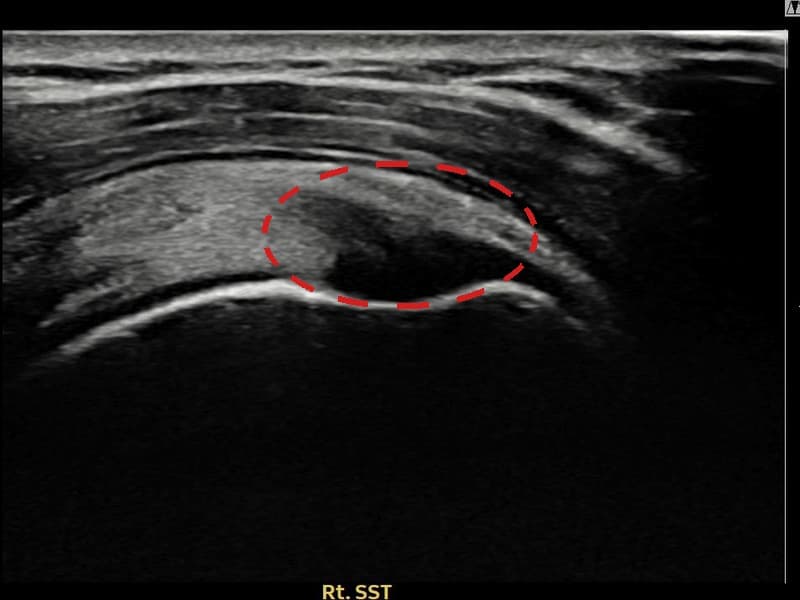

术前

术前超声确认右侧 冈上肌腱 关节面侧部分撕裂,右侧冈上肌腱回声不连续伴肌腱缺损(7mm × 4mm (肌腱厚度约42%缺损))。术后超声显示撕裂部位充满再生组织,肌腱连续性恢复,回声模式正常化。

该患者持续肩痛。详细超声检查确认右侧 冈上肌腱 关节面侧部分撕裂(缺损:7mm × 4mm (肌腱厚度约42%缺损))。在超声引导下实施非手术缩小缝合术。术后佩戴支具约4-6周,随后进行分阶段康复锻炼。随访超声确认肌腱连续性恢复、结构稳定,患者顺利回归日常生活。